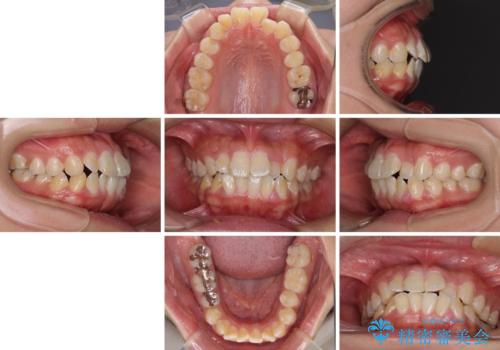

- 前歯のクロスバイトと、口元が閉じにくいとのことで来院された患者様です。

口元の突出感を改善する必要があるため、上下左右の第1小臼歯4本を抜歯し、ワイヤー装置にて矯正治療を行うこととしました。